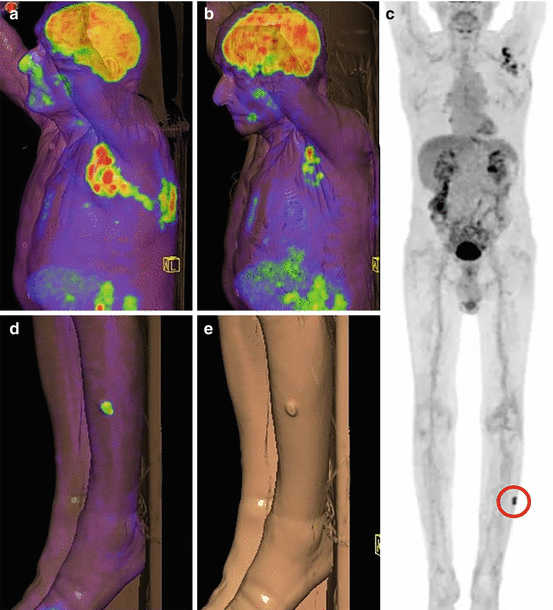

MIP PETCT images for patients with metastatic melanoma (a) Patient Pet Ct Scan For Melanoma Positron emission tomography (pet) scan. A pet scan can help show if the cancer has spread to lymph nodes or other parts of the body. Pet Ct Scan For Melanoma.